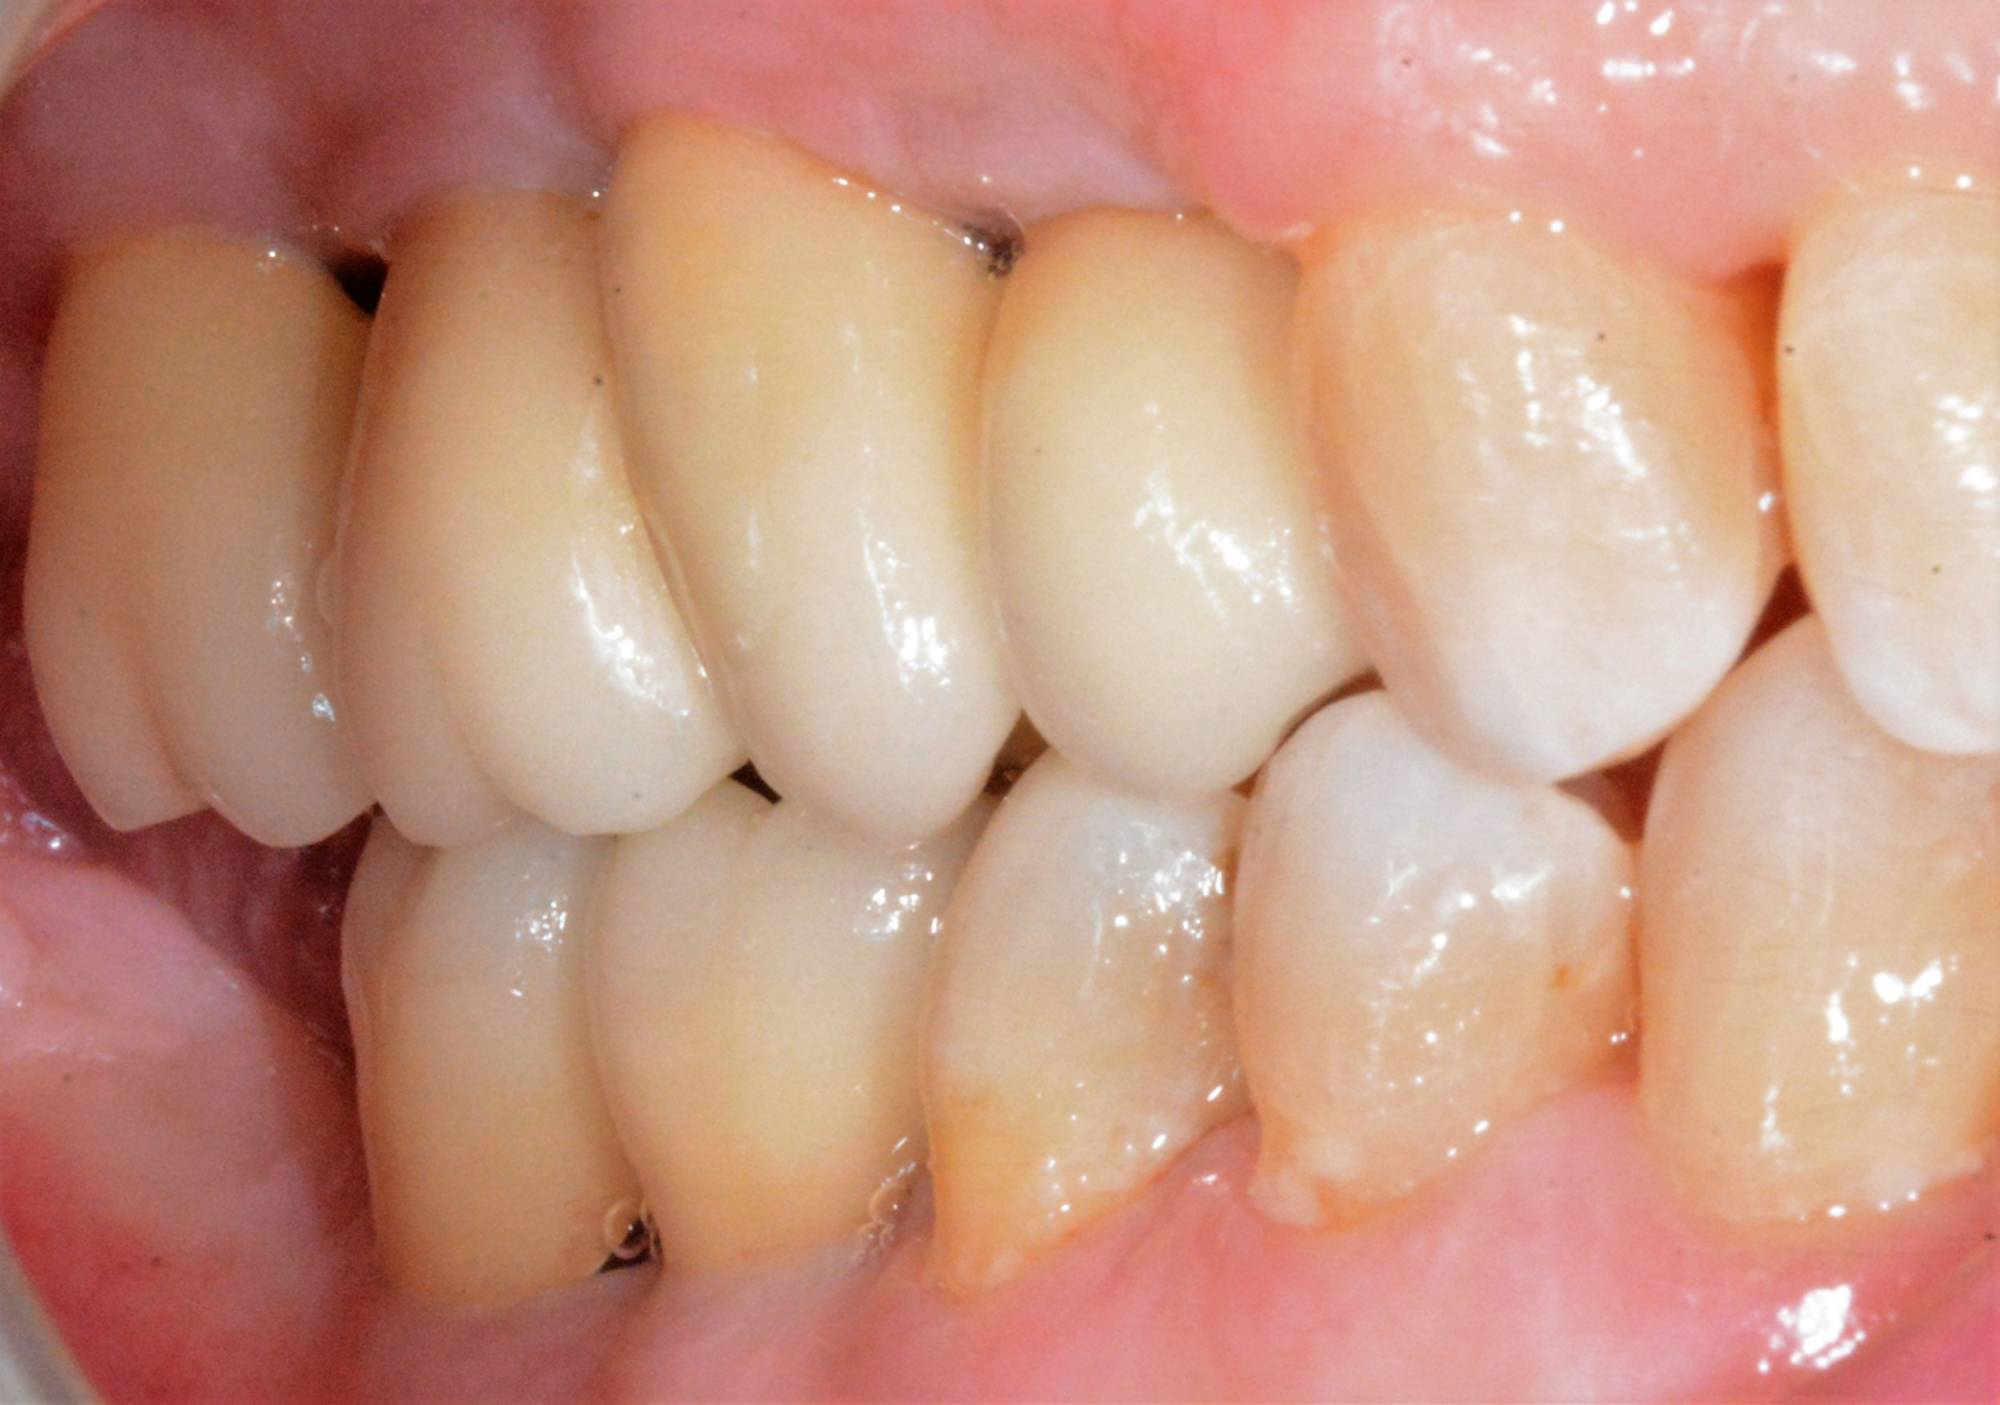

L'impianto, oltre a essere un metodo sicuro, garantisce l'aspetto esteriore e la piena funzionalità di un dente naturale. Oltre a ciò, mantiene l’integrità dell’osso, non va ad intaccare i denti adiacenti - come invece farebbe un ponte - e migliora l’estetica facciale prevenendo la perdita ossea.

Gli impianti sono molto versatili e possono essere usati per sostituire un dente singolo, più denti fissi o addirittura un'intera arcata. Inoltre, possono essere inseriti sotto una protesi mobile per stabilizzarla migliorandone il comfort.